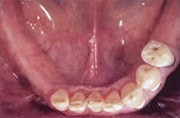

Früher wäre hier nur eine herausnehmbare Teilprothese infrage gekommen.

Fehlen mehrere Zähne, so spricht man vom teilbezahnten Kiefer. Solche größeren Zahnlücken konnten früher oftmals nur mit herausnehmbaren Teilprothesen geschlossen werden, wenn eine Brückenversorgung nicht mehr möglich war. Implantate erlauben, die Lücke mit einer implantatgetragenen festsitzenden Brücke zu schließen, ohne herausnehmbare Prothesen und ohne Abschleifen gesunder Nachbarzähne.

herausnehmbare Teilprothese mit Klammern